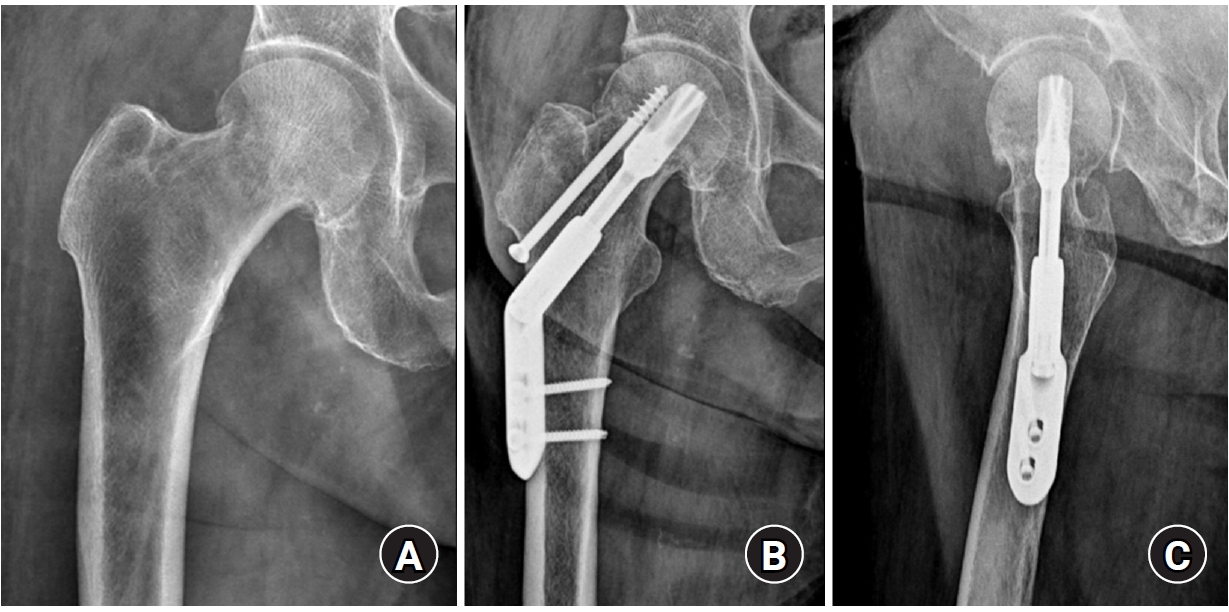

Complications occurred in a total of three cases (12.5%) in the FNS group, which included two cases of fixation failure and one case of AVN. In the DHS group, complications also occurred in three cases (12.5%), consisting of one case of nonunion and two cases of AVN. There was no significant difference in the overall complication rate between the two groups (P=1.000). All patients who experienced complications (six patients) required conversion to arthroplasty (Table 3, Fig. 4).

The complication rate was also identical in both groups at 12.5%, which is within an acceptable range compared to other large-scale studies. Davidson et al. [10] reported a reoperation rate of 15.7% in their analysis of 102 FNS patients, and Stassen et al. [5] reported a mechanical failure rate of 9.3% in a one-year follow-up study. The two cases of fixation failure in our FNS group may be related to the poor bone quality of the osteoporotic elderly patients or surgical technique, rather than to an inherent problem with the implant itself. Several biomechanical studies have emphasized that the stability of the FNS is highly dependent on the precise central placement of the implant within the femoral neck [7,16]. Especially in elderly patients with low bone mineral density, accurate implant positioning is crucial to prevent fixation failure, particularly the 'cut-out' phenomenon. Furthermore, Cha et al. [17] have pointed out that the 5-mm increments in the FNS bolt length can make fine adjustments of the insertion depth difficult and have proposed a surgical technique to compensate for this. Therefore, a thorough understanding of and attention to these technical aspects are required to achieve successful clinical outcomes with the FNS.

Fig. 4.

(A) A 64-year-old female patient sustained a stable femoral neck fracture on the left side. (B) The fracture was treated with the femoral neck system (FNS; anteroposterior and axial view). (C) A postoperative 6-month radiograph shows fixation failure of the FNS.

Fig. 4. (A) A 64-year-old female patient sustained a stable femoral neck fracture on the left side. (B) The fracture was treated with the femoral neck system (FNS; anteroposterior and axial view). (C) A postoperative 6-month radiograph shows fixation failure of the FNS.